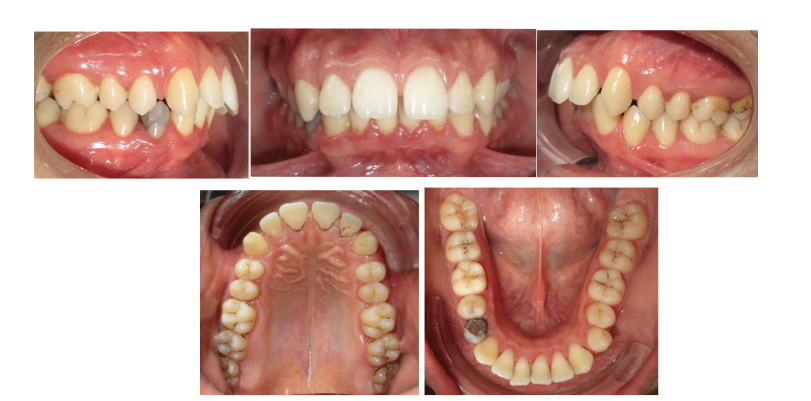

The patient M.E., a 29-year-old male, presented to the Dentofacial Orthopedics Department of the Casablanca University Hospital with a functional complaint of recurrent obstructive sleep apnea, negatively impacting his quality of life. He also reported a gummy smile and a marked mandibular retrognathia. The patient had previously undergone orthodontic treatment, but experienced a relapse.

Clinical evaluation revealed an oval, elongated, and symmetrical face with a convex facial profile. Lip closure at rest was incomplete and required hyperactivity of the mentalis muscle. The patient had a short upper lip and an obtuse nasolabial angle. Vertically, the lower third of the face was predominant compared to the middle and upper thirds.

The patient demonstrated moderate oral hygiene. The upper and lower dental midlines were centered and coincident with the facial midline. The molar and canine relationships were classified as Angle Class II, with no dental crowding in either arch. The maxillary arch was broad, with an interincisal diastema and protruded upper incisors. The mandibular arch was U-shaped, with vestibular inclination of the lower incisors. A restoration was noted on tooth 44, along with a diastema between teeth 33 and 32.

• Panoramic radiograph: The panoramic radiograph revealed a complete dentition with no signs of alveolar bone loss. The mandibular condyles showed normal morphology, with no clinical or radiographic signs of temporomandibular joint dysfunction. A restoration and a root canal treatment were observed on tooth 44.

• Lateral cephalometric radiograph: Cephalometric analysis showed features of posterior mandibular rotation, with GoGn/SN = 46° and FMA = 43°. Steiner and Tweed cephalometric measurements confirmed a skeletal Class II pattern, with pro-alveolar upper incisors and retro-alveolar lower incisors.